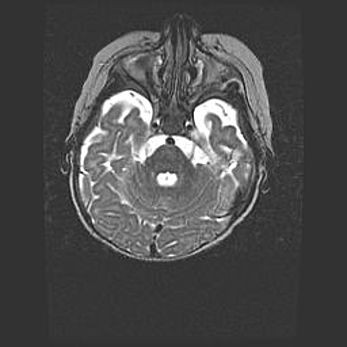

Церебральная ишемия II.

Возраст: 5 дней

Вес: 3400 г

Пол: женский

Окружность головы: 35 см

Срок гестации: 39 недель

Церебральная ишемия – это заболевание, характеризующееся недостаточностью (гипоксией) либо полным прекращением (аноксией) снабжения мозга кислородом по причине закупорки одного или нескольких сосудов. Это приводит к  что метаболическим расстройствам различной степени тяжести в тканях головного мозга, развитию коагуляционных некрозов и гибели нейронов.